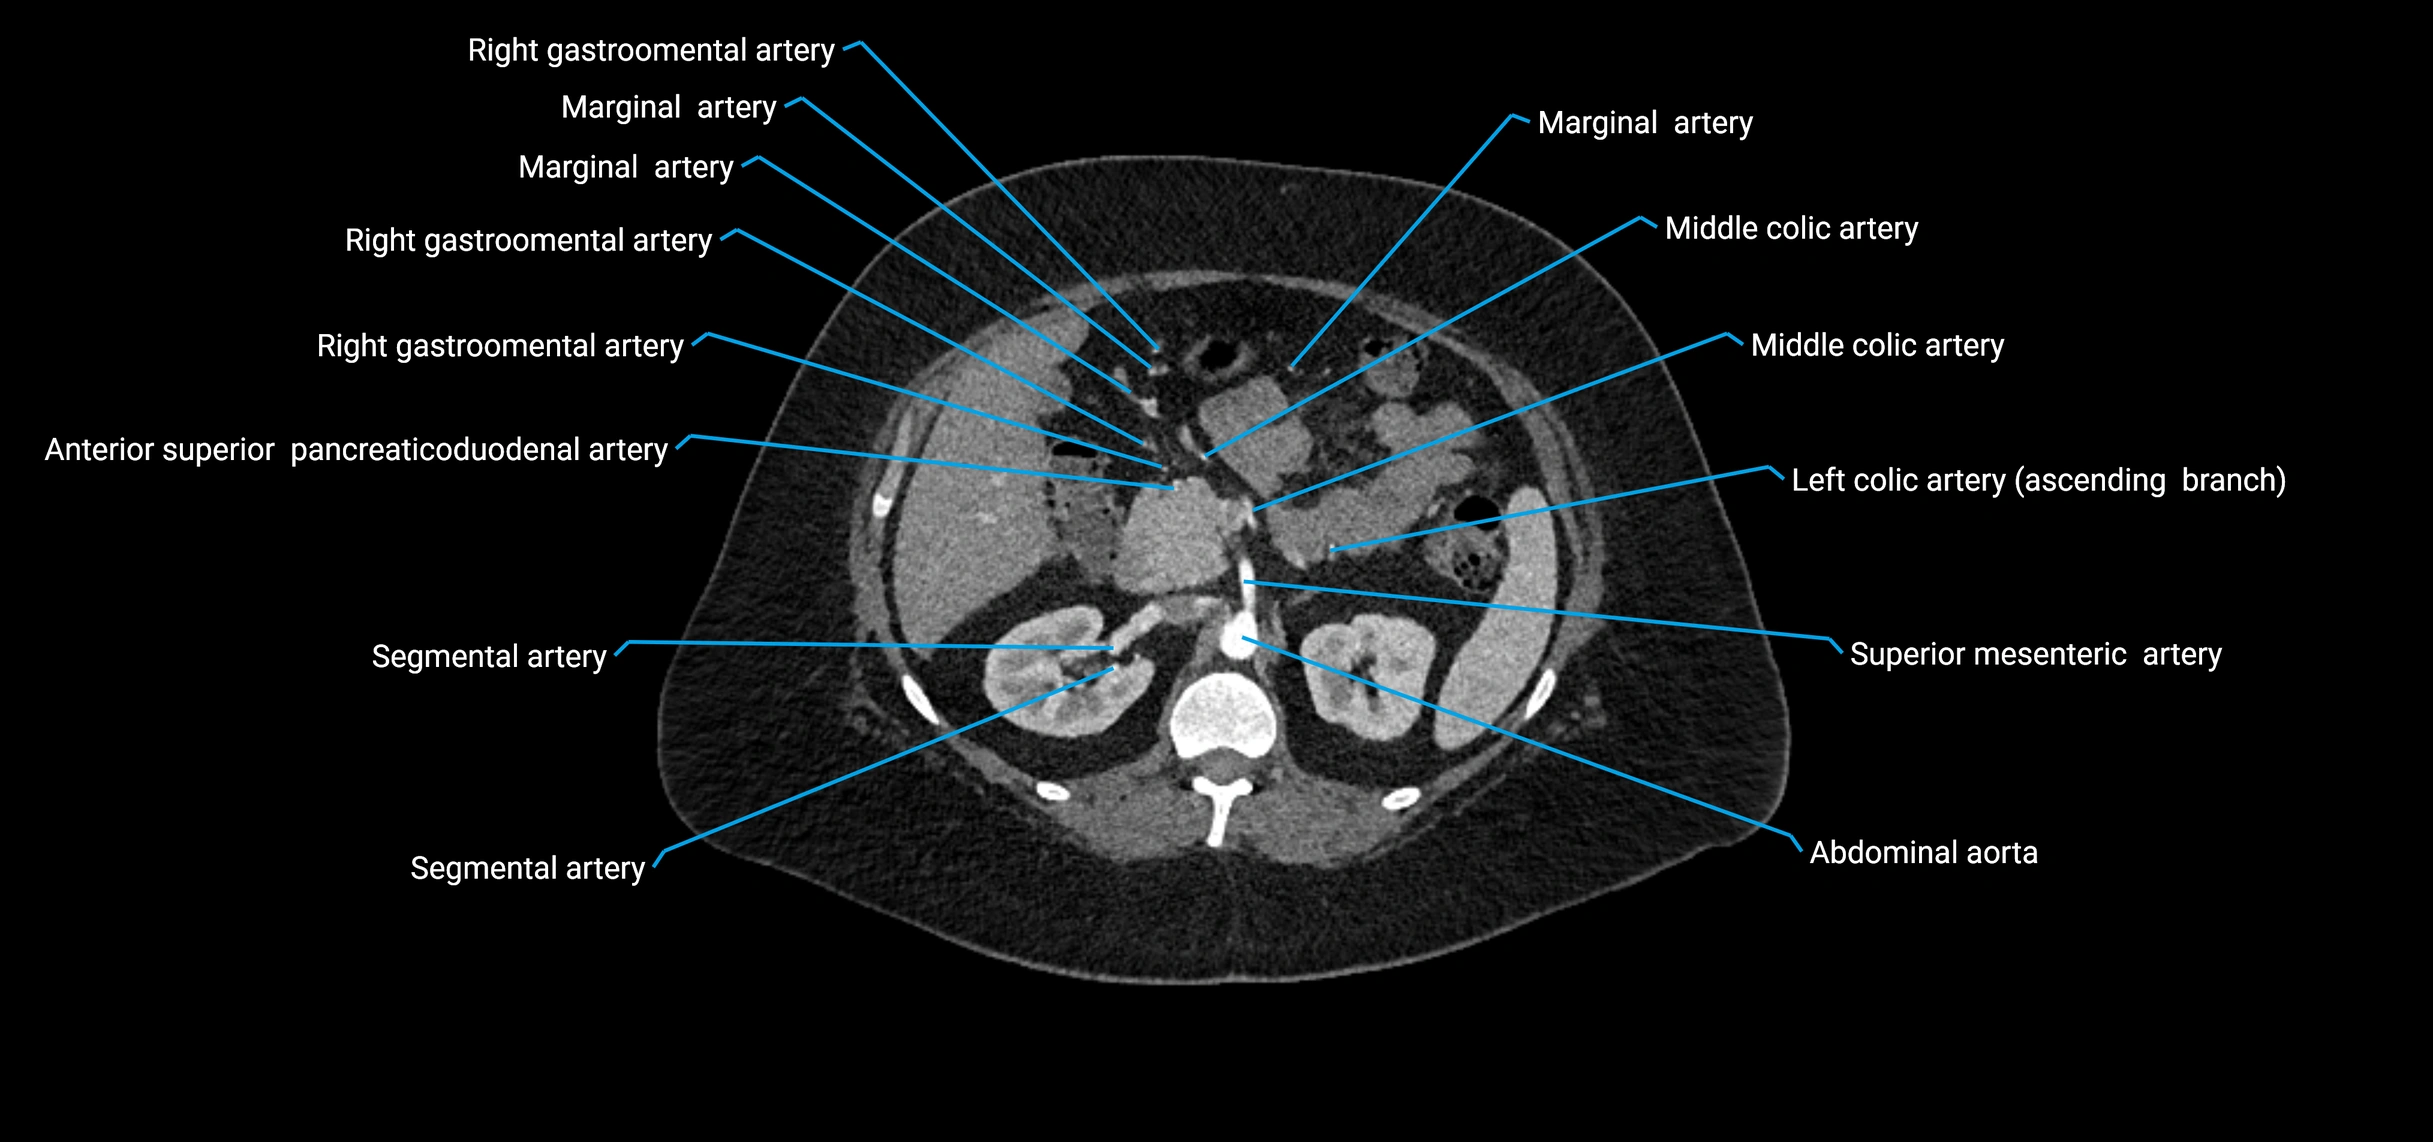

• Unpaired visceral branches: celiac trunk, superior mesenteric artery (SMA), inferior mesenteric artery (IMA)

• Paired visceral branches: middle suprarenal arteries, renal arteries, gonadal arteries (testicular or ovarian)

CT images

image